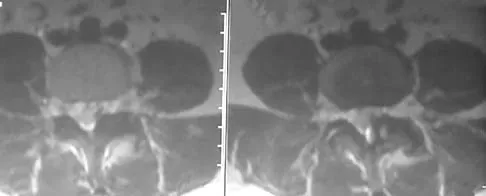

Figure 10 shows the MRI scan of a 56-year-old woman with metastatic breast cancer who now reports progressive paraparesis. Her general health remains good. Treatment should consist of

A 40-year-old woman has had sciatic pain on the left side for the past 8 weeks. She reports that the pain radiates to her posterior thigh, lateral calf, and into the dorsum of her left foot. Neurologic examination shows weakness of the left extensor hallucis longus. Axial T2-weighted MRI scans through L4-L5 are shown in Figure 14. Management should consist of

A 56-year-old woman with a history of metastatic breast cancer presents with progressive paraparesis and hyperreflexia in her lower extremities over the last 3 days. Her systemic disease is otherwise well-controlled, and her expected survival is greater than 1 year. MRI reveals a pathological fracture at T8 with high-grade epidural spinal cord compression caused by tumor mass. Based on the Patchell trial criteria, what is the most appropriate initial treatment?